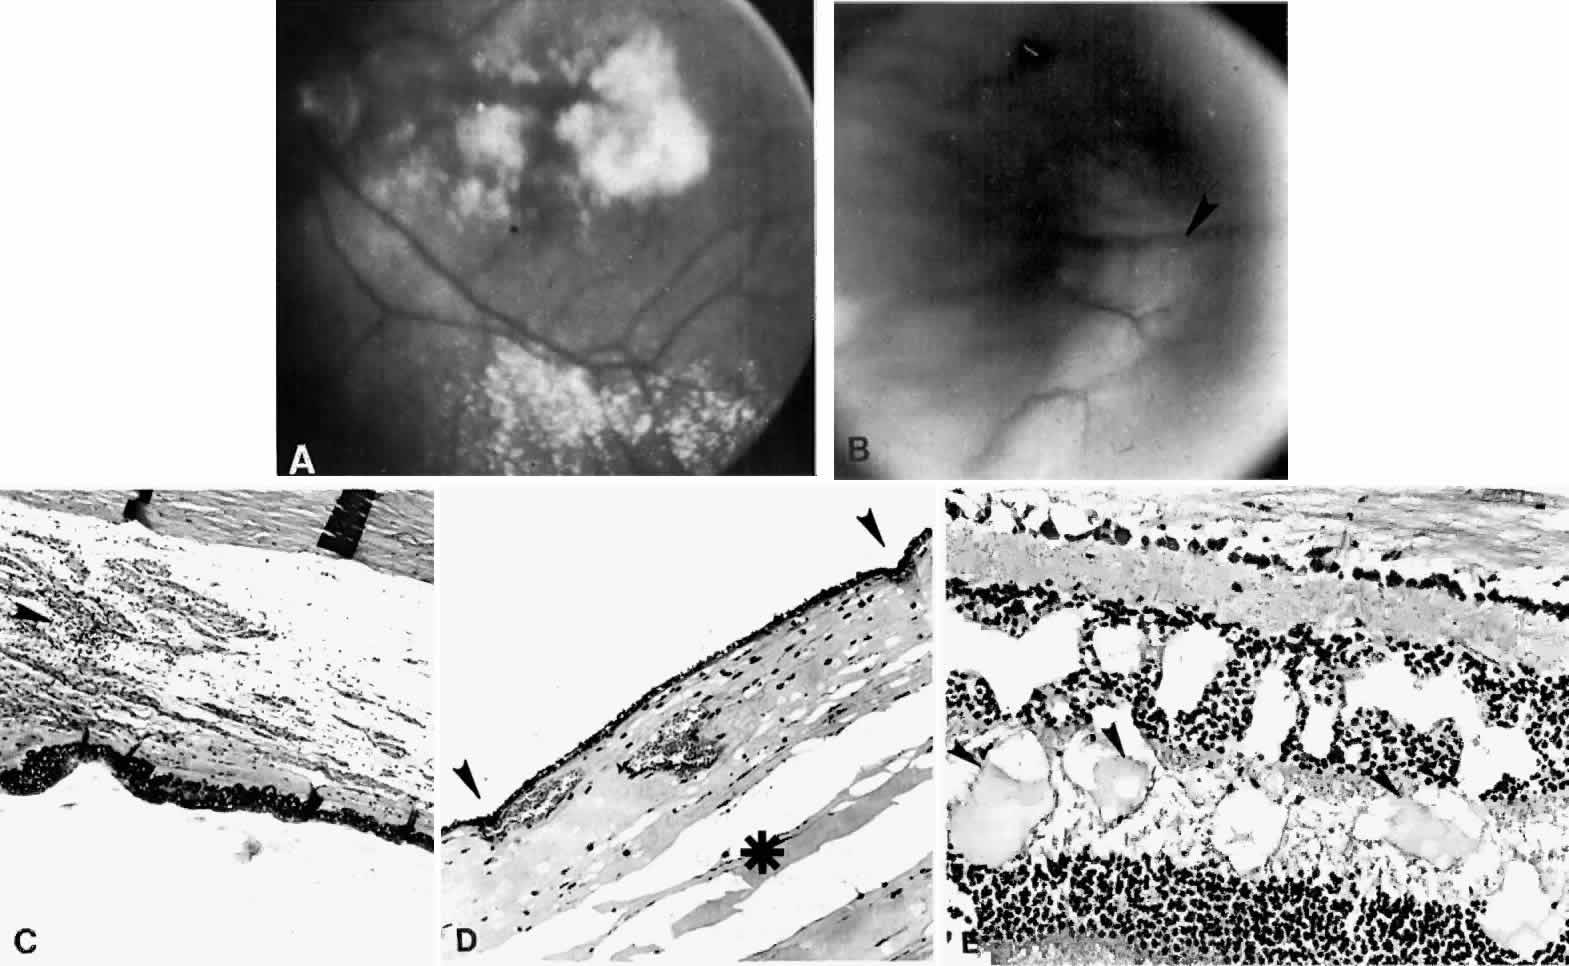

Fig. 8. This choroidal and ciliary body detachment, which occurred after intracapsular cataract extraction, was mistaken for a malignant melanoma.39 A. Iris incarceration in the wound (arrow) and extensive ciliary body effusion consisting of a dense, proteinaceous material (asterisk) (H & E, × 115). B. Effusion of the choroid near the ora serrata by a moderately dense, proteinaceous material without inflammatory cells. Note folds of choroid (arrowheads) (H & E, × 115).

Various surgical procedures may be complicated by a ciliochoroidal effusion during or after the procedure. An expulsive effusion can mimic an expulsive hemorrhage during cataract extraction33–36 or glaucoma surgery, especially in patients with prominent preoperative episcleral vessels, as in Sturge-Weber syndrome.37 Varying degrees of postoperative suprachoroidal edema may develop after cataract extraction (Figs. 7 and 8),1,9,32–34,38–46 iridectomy (Fig. 9), filtering procedures (Fig. 10),1,9,32,37,47–49 retinal detachment surgery (Fig. 11),50–54 panretinal photocoagulation,55,56,56a or cryotherapy. A postoperative ciliochoroidal effusion can occur weeks, months, or even years after surgery.40,57 Between 1 and 18 months after filtration surgery, hypotony and ciliochoroidal detachment developed in four patients when timolol or acetazolamide therapy was instituted.57

Fig. 9. A. This serosanguineous ciliochoroidal effusion (arrow), which occurred after iridectomy for an iris melanoma in a 68-year-old man, was mistaken for a choroidal melanoma (H & E, × 25). B. Site of the limbal wound (arrowhead) with incarceration of the iris base and residual melanoma in the iris, anterior aspect of the ciliary body, and trabecular meshwork (H & E, × 60).

Fig. 10. A. This extensive ciliochoroidal effusion (asterisk), which occurred 4 years after iridencleisis in a 70-year-old man,39 was mistaken for a malignant melanoma. The iris (arrow) is incarcerated in the limbal wound, and a flat, edematous infiltration bleb (arrowheads) is present (H & E, × 25). B. Area of the ora serrata shows a ciliochoroidal effusion with proteinaceous material separating the tangentially oriented collagen fibers (arrowheads) that connect the choroid and ciliary body to the sclera (H & E, × 115).